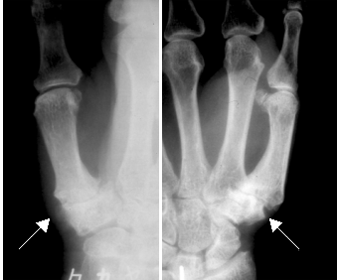

レントゲン検査でCM関節に「隙間が狭い」「軟骨が硬くなってトゲの様になっている(骨棘)」「亜脱臼」などの変形が見られた場合に、CM関節症と診断されます。

CM関節症